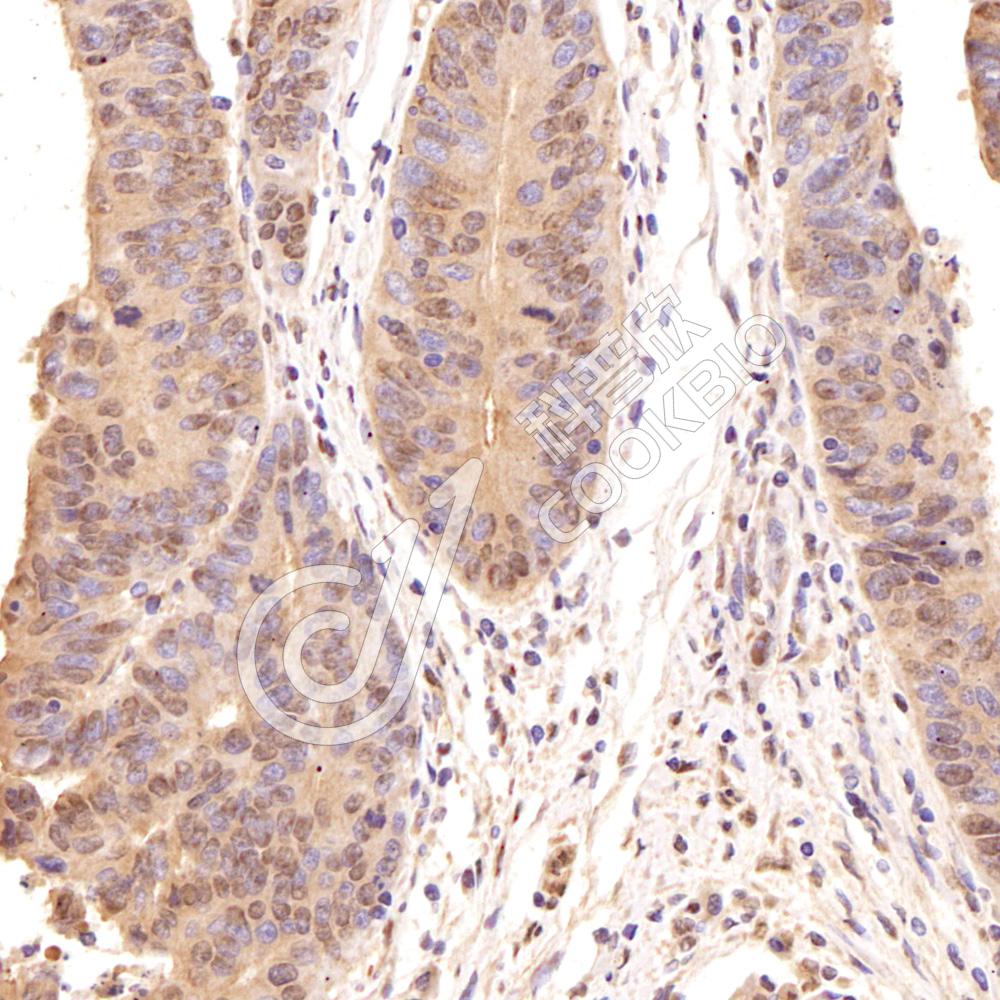

IHC检测Phospho-GSK3 Beta(S9)蛋白(货号 K5450150).

样品: 人结肠癌, 4%多聚甲醛 (货号KSG1101) 固定12-24小时.

抗原修复: 柠檬酸抗原修复液(干粉, pH 6.0) (KSG1201), 高压锅均匀喷气计时2分钟.

—抗: 1: 500稀释, 4℃ 孵育过夜.

二抗: S-vision免疫组化多聚二抗(山羊抗兔),即用型 (货号KB3906), 室温孵育20分钟.